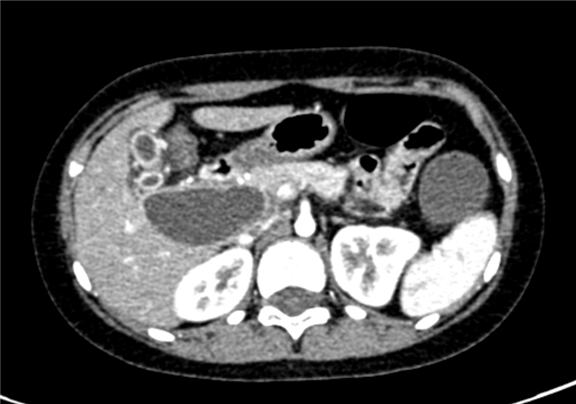

上腹部增强CT:先天性胆管囊状扩张(IV型)可能性大,胆总管十二指肠胰腺段及十二指肠壁内段显示不清, 胆囊壁增厚,肠系膜根部散在散在略大淋巴结

术前CT检查:

动脉期

静脉期